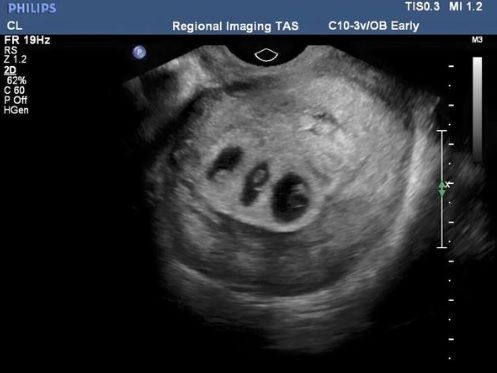

Soarta a făcut ca, în scurt timp, Chloe să rămână însărcinată. Nefiind la prima sarcină, tânăra a mers, prevăzătoare, la control, pentru a se asigura că bebeluşul este bine. La scurt timp după ce a păşit în cabinet, doctorul i-a dat o veste care a şocat-o! Ecografia îi arăta că urma să aducă pe lume încă trei bebeluşi!

În săptămâna 28 de sarcină, Chloe a mers la un nou control. A aflat atunci că avea în pântec doi băieţi şi o fetiţă. Din nefericire, nu era singura veste pe care aveau să i-o dea medicii... Fetiţa era slab dezvoltată şi toate semnele indicau că nu va supravieţui... Disperaţi, medicii au căutat o soluţie pentru a salva viaţa fetiţei. La un moment dat, au găsit-o, dar asta însemna ca mama să intre imediat în operaţie. Procedura, însă, punea viaţa băieţilor în pericol. Astfel, Chloe s-a văzut pusă în situaţia în care trebuia să aleagă care dintre cei trei copii va supravieţui: fetiţa sau băieţii?